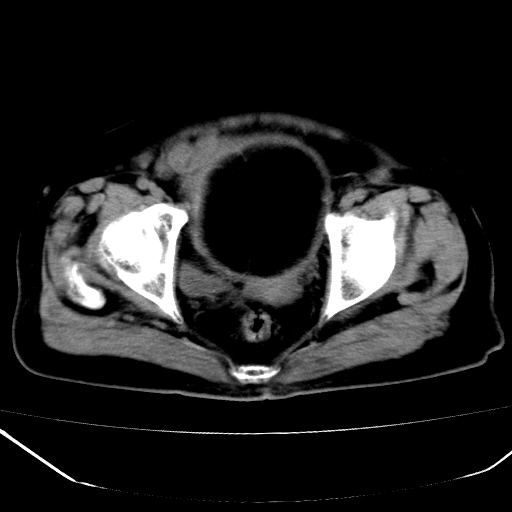

标题: CT18557:盆腔内包块,请指教

患者,女,74岁,无不适,b超示盆腔包块。

子宫前上方巨大脂性肿物,肿物边缘为较厚软组织密度影,其内缘欠光整,脂性密度中央见结节状软组织密度影“漂浮”,肿物与子宫前壁关系密切,考虑1脂肪瘤2皮样囊肿3肌瘤脂样变

ct值-90hu